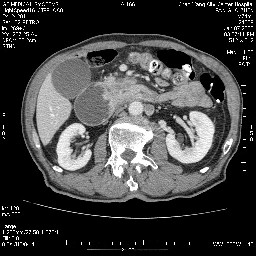

女,74岁,呕吐10余日

考虑来源于十二指肠水平段的恶性占位,侵及周围组织,特别是胰腺,可见区域淋巴结肿大,左侧下腔静脉畸形。

双肾多发小囊肿;左肾积水。

十二指肠水平段腔内占位伴梗阻,中等度较为均匀的强化,洗脱慢,区域淋巴结显示增多,符合腺癌表现。下腔静脉变异。

支持十二指肠腺癌伴梗阻.,下腔静脉发育变异.

十二指肠降段扩张,水平段狭窄成鼠尾状,肠壁明显增厚,胰腺勾突增大成不均匀强化,其内可见低密度区,胆囊增大,1十二指肠水平段腺癌侵犯胰腺勾突可能大,2胰腺癌侵犯十二指肠(只有胆囊增大没有肝内外胆管扩张不好解释)代除外.

需除外12指肠水平段间质瘤。

十二指肠水平部腺癌伴梗阻并侵犯邻近结构。下腔静脉发育变异。

十二指肠降段扩张,水平段狭窄成鼠尾状,肠壁明显增厚,胰腺勾突增大成不均匀强化,其内可见低密度区,胆囊增大,1十二指肠水平段腺癌侵犯胰腺勾突可能大,2胰腺癌侵犯十二指肠 。

今日手术结果:胰腺钩突癌侵犯十二直肠,腹腔淋巴结转移.